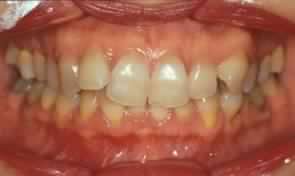

Le manifestazioni cliniche ed i disturbi che vengono conseguenti la malocclusione, sono fenomeni a cascata che possono essere osservati e documentati:

• Abrasioni degli elementi dentari sottoposti a trauma

• Recessioni gengivali

• Recessioni parodontali, fino alla Malattia Parodontale o piorrea